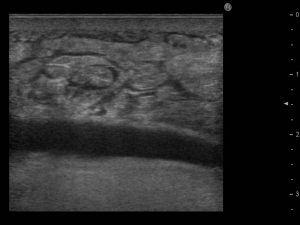

そして、BRAVA使用後に行ったエコー検査で、こちらの衝撃の画像を目の当たりにしました。

脂肪の層の下に黒く見える部分、これは以前、豊胸シリコンバッグが挿入されていたスペース(ポケット)です。なんとシリコンバッグを抜去(摘出)後、10年経過しても塞がっていなかったのです。エコーは断面図なので、通常、薄く広がるポケットの存在は映りません。しかしこの方の場合はBRAVAの陰圧により一次的にポケットが拡張され、空洞が黒く映し出されたと考えられます。

ポケット完全に癒着して塞がっていれば、陰圧をかけても裂けて広がることはまずないので、このように見えることはなかったでしょう。こちらのエコー画像は「一度できたポケットが塞がる確証はない証拠」として、医学論文でも紹介しました。